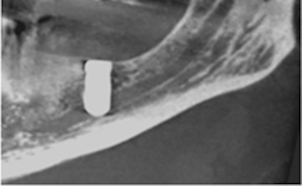

Das Verfahren der vollständig MRT-basierten, schablonengeführten Implantation wurde maßgeblich am Klinikum rechts der Isar in der Abteilung für Neuroradiologie in Kooperation mit der LMU-Poliklinik für Zahnärztliche Prothetik sowie der LMU-Poliklinik für Mund-, Kiefer- und Gesichtschirurgie entwickelt. Diese Technik ermöglicht eine komplett strahlenfreie schablonengeführte dentale Implantation. Durch die direkte Darstellung des Nervus alveolaris inferior, welche nur durch MRT möglich ist, bietet dieses Verfahren die größtmögliche Sicherheit für den Patienten.

Sollte es zu einer Schädigung des Nervus alveolaris inferior oder des Nervus lingualis gekommen sein, wie in dem Bildbeispiel durch Fehlpositionierung eines dentalen Implantats durch den Mandibularkanal, lässt sich der Nervenschaden durch MRT direkt darstellen und graduieren. Somit kann schnellstmöglich eine Diagnose gestellt und Therapieoptionen evaluiert werden.